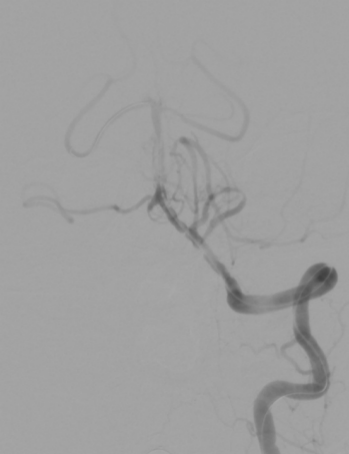

入院颅脑CT未见明显异常;头颈CTA提示基底动脉闭塞;

DSA示:基底动脉下段闭塞。